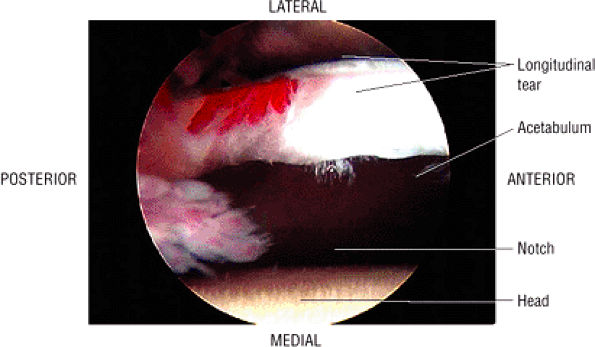

patient. Unfortunately, the hypertrophic labrum is exposed to greater joint reaction forces and is at an increased risk for symptomatic tearing. The acetabular labrum may also become inverted, entrapped, and subsequently torn. Direct contact between the hypertrophied labrum and the femoral head chondral surface may produce a chondral crease demarcating a femoral head bump formed proximal to the physeal scar. This finding is associated with a lateral acetabular rim or the DDH equivalent of FAI. Anterior coronal MR images evaluated at the level of the anteriormost portion of the femoral head are sensitive to asymmetry in the slope of the acetabulum. The anterior acetabular roof should maintain a relatively horizontal slope and not open up or deviate from the horizontal plane.

FIGURE 3.101 ● (A) DDH associated with longitudinal tearing of a hypertrophied labrum. The shallow slope of the acetabulum is demonstrated. The transverse angle of the osseous acetabular rim affects the degree of lateral coverage and is increased in adult DDH. (B) The normal angle of 40° is shown in contrast to (A).